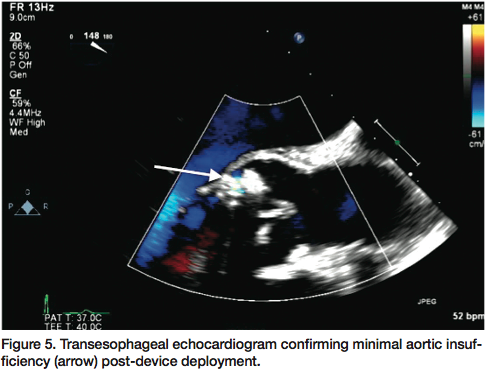

defect (Figure 3). The two proximal lobes of the device were then packed against the aortic side of the defect and with adequate positioning confirmed, the delivery system disengaged and final angiographic (Figure 4) and transesophageal images obtained, demonstrating no significant aortic insufficiency (Figure 5). All catheters and sheaths were removed, with hemostasis achieved using a vascular closure device. The patient was discharged home the following day without any complications.